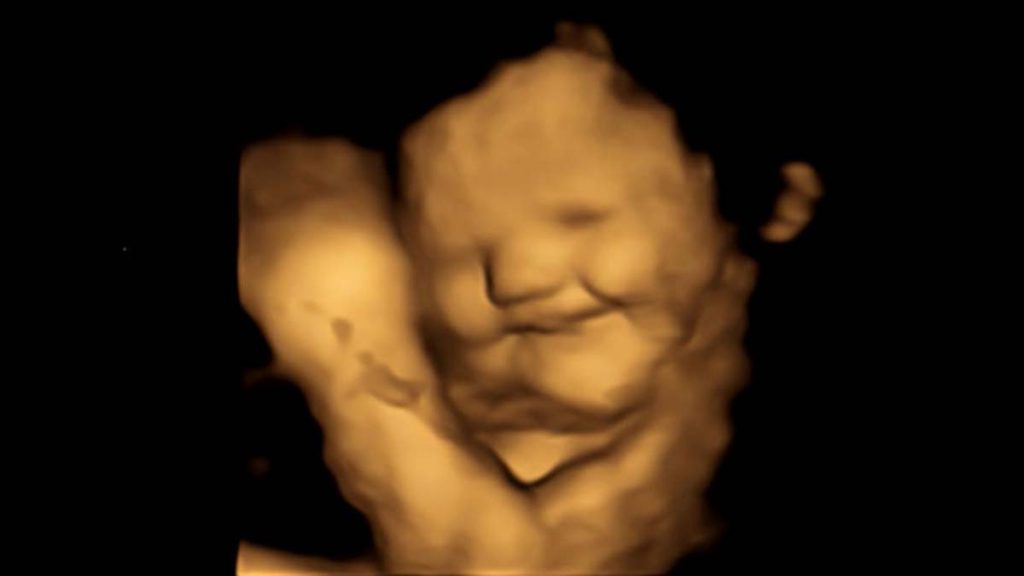

Con ecografías realizadas en 4D, investigadores analizaron reacciones faciales de los bebés ante ciertos alimentos.

Un grupo de científicos captó la expresión facial de bebés dentro del útero ante la ingesta de ciertos alimentos por parte de la madre. Para ello, emplearon ecografías 4D con un resultado sorprendente.

En el caso de la zanahora, los fetos mostraron "cara de risa", aunque en el caso de la col obtuvieron "cara de llanto", dijo la casa de estudios.

"Fue realmente sorprendente ver la reacción de los bebés no nacidos a los sabores de la col rizada o la zanahoria durante las exploraciones y compartir esos momentos con sus padres", explicaron los investigadores.